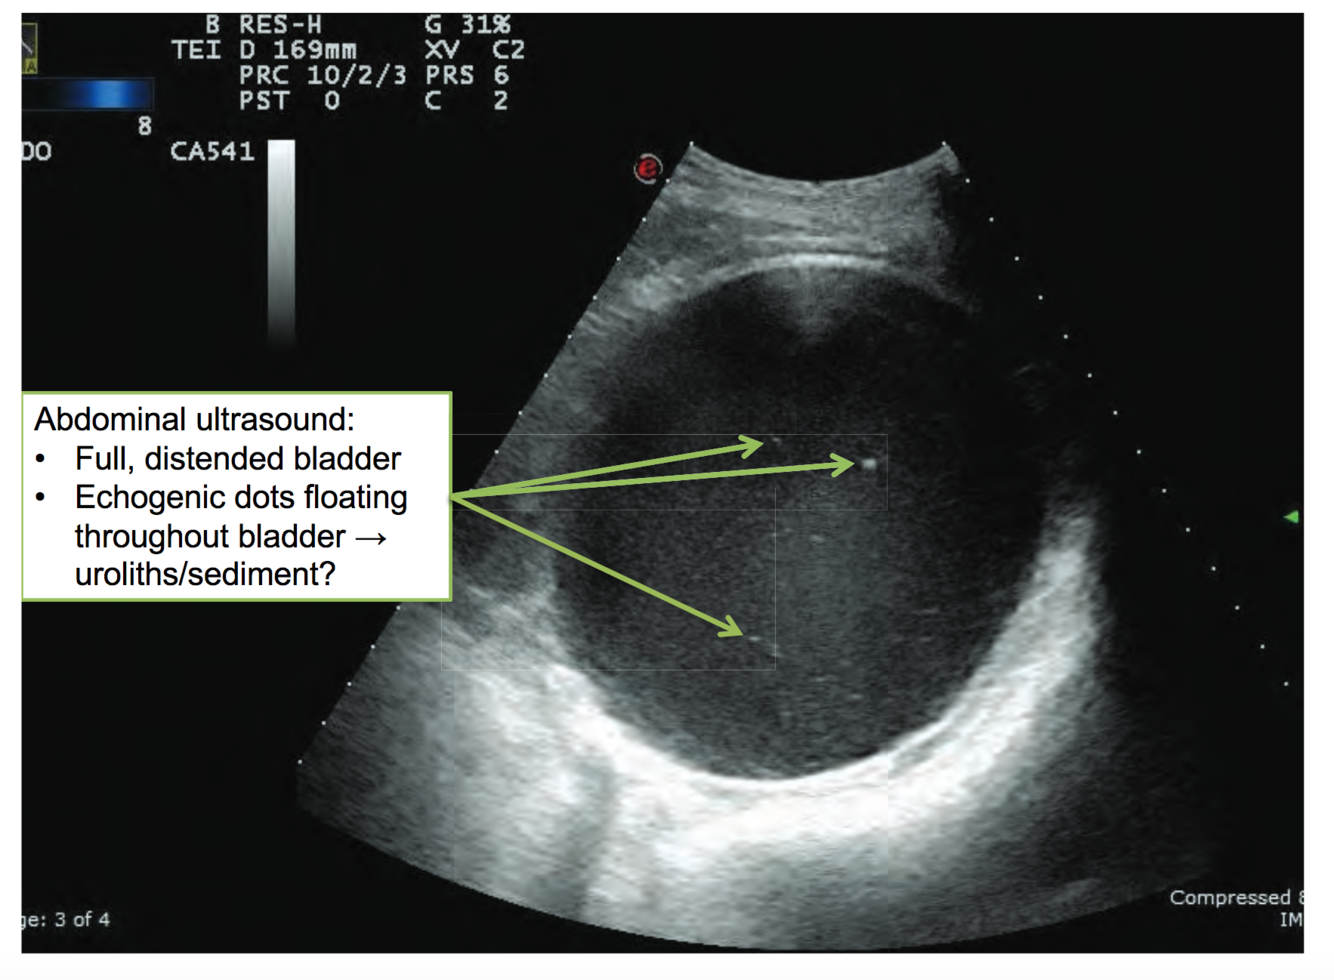

Sheep with urinary tract problems may show…

Urolithiasis: Clinical Signs